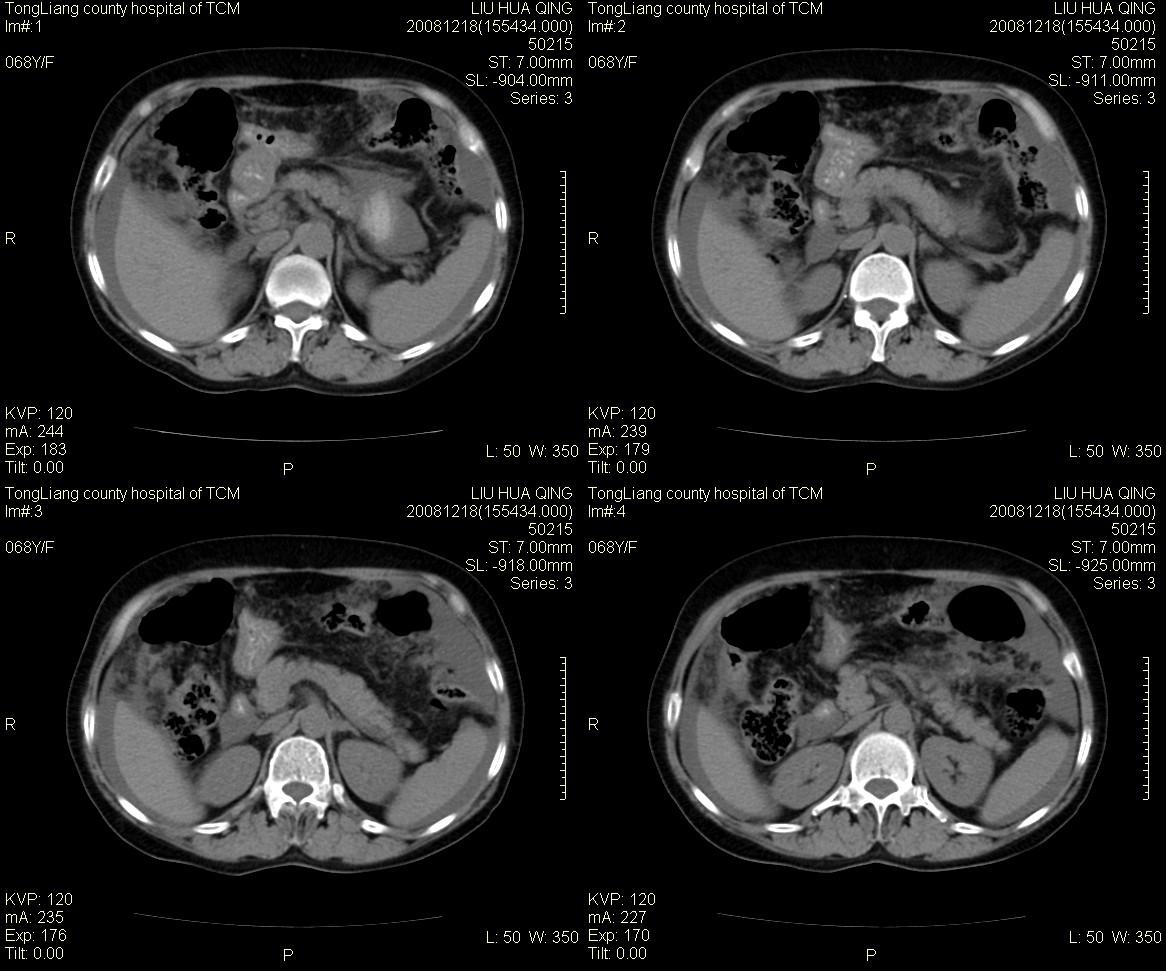

女,68y,下腹疼3月,一月半前院外ct示上腹未见异常。近1月来,症状加重。4天前入院,b超示胸腹水。今日呕吐频繁。  生化检查:  结核抗体阴性,血沉18mm/h, 癌胚抗原阴性,胸水细胞学检查见多数淋巴细胞。 白细胞总数5.4x10^12/l,血红蛋白104g/l.

患者右中腹部肠管聚集,内密度不均,可见片絮状及结节样增密影,小肠壁增厚,与之相邻处有软组织影。

腹腔积液可以肯定,原因?右侧下腹肠壁增厚,周围脂肪密度增高,粘连坏死?---梗阻坏死(不像)还是血栓坏死,占位?期待结果。

1)右侧腹腔前部见类似“网膜饼”样改变,考虑网膜转移瘤。2)腹水。

腹膜污染[大网膜增厚可见污垢征及小班结与饼片影,肠系膜增厚],大量腹水。考虑癌性腹膜炎,建议查腹水。结核待排.注意上腹部及胃肠道检查